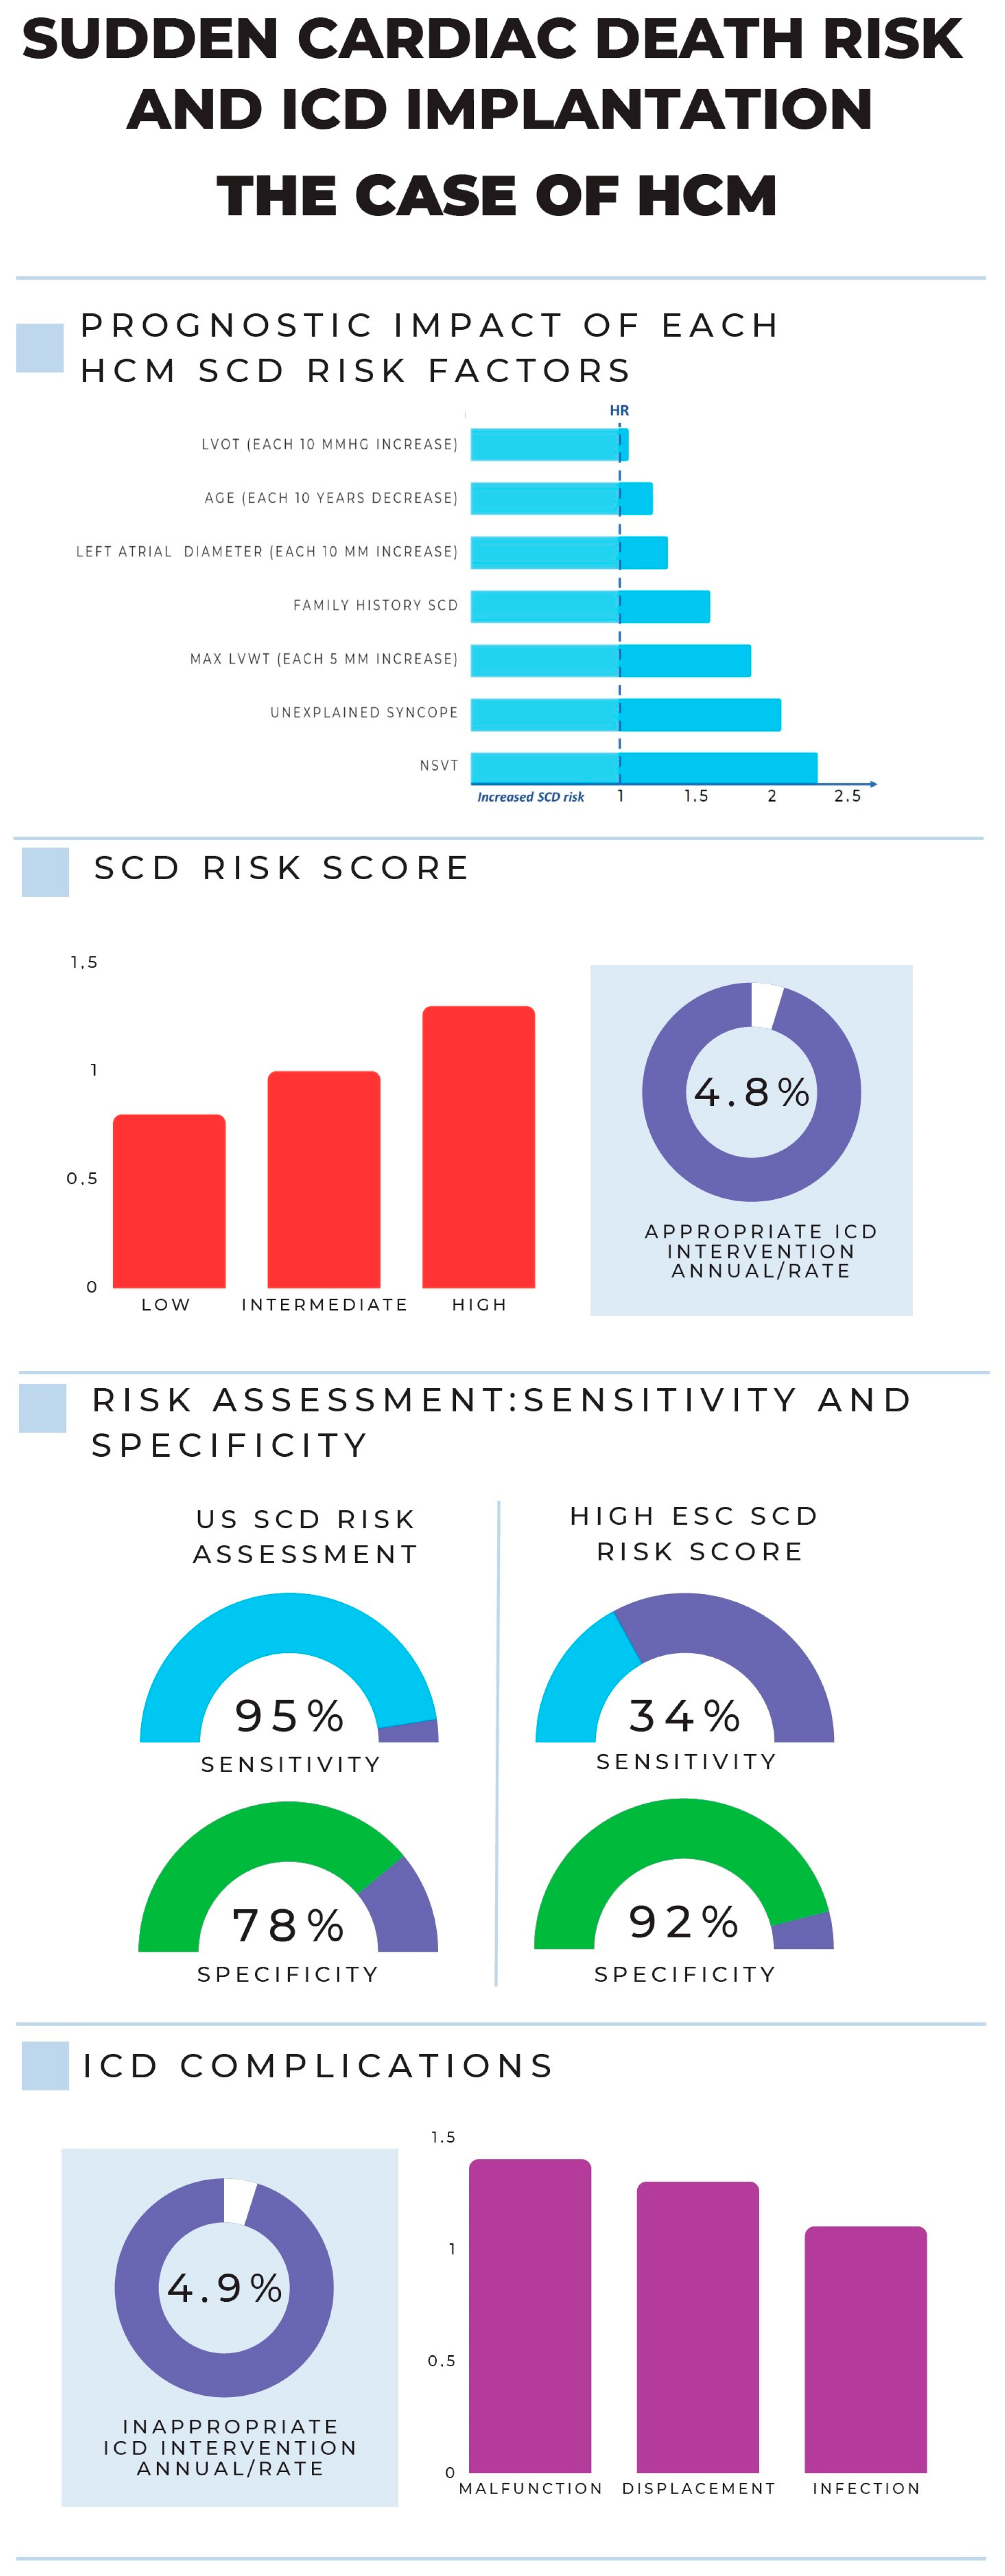

1.2. Sudden Cardiac Death Risk in Cardiomyopathies: From a Traditional Viewpoint to a Personalized Approach

2. The Hierarchical and Multiparametric Approach of SCD Risk Estimation in Cardiomyopathies

3.3. ICD Implant in Cardiomyopathies